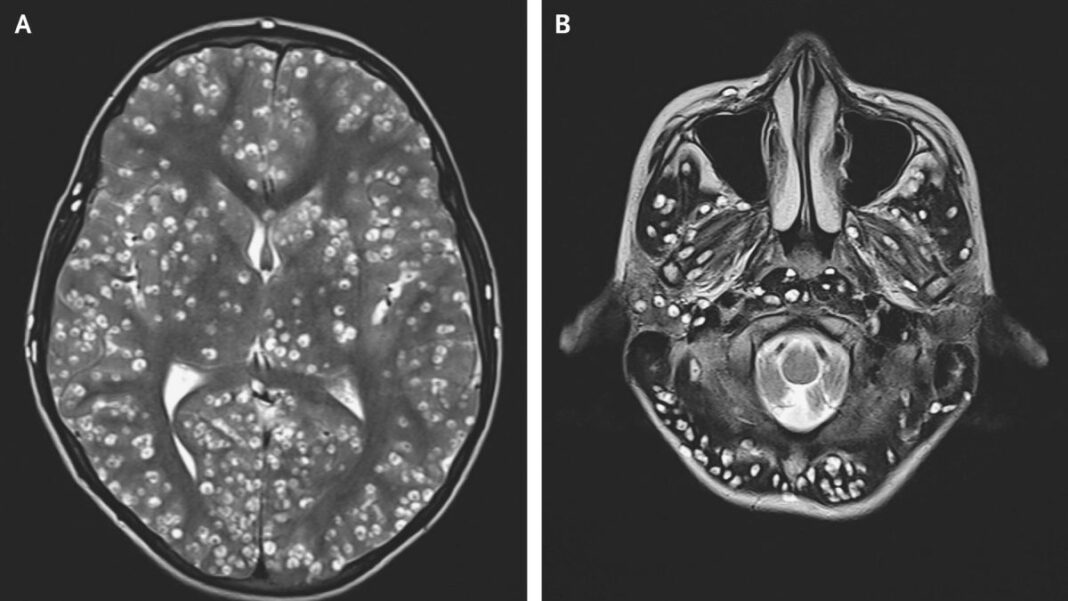

As autópsias que foram realizadas nos soldados humanos mortos revelaram que eles estavam infestados por um pequeno verme parasita preto que se aloja em seus cérebros, especialmente ao redor das órbitas oculares, no nervo óptico e, em alguns casos, dentro do próprio globo ocular. Era um verme geneticamente modificado e altamente sofisticado, baseado no Taenia solium da Cisticercose. Este verme geneticamente modificado destrói o córtex frontal por meio de invasão física e pelo uso de uma neurotoxina secretada.